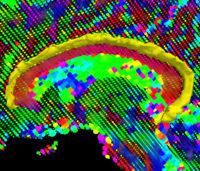

Multimodal Deformable Registration of Traumatic Brain Injury MR Volumes using Graphics Processing UnitsTime-efficient processing and analysis of magnetic resonance imaging (MRI) volumes is desirable is for the neurocritical care and monitoring of traumatic brain injury (TBI) patients. An important problem of TBI neuroimaging data analysis is the task of co-registering MR volumes acquired using distinct sequences in the presence of widely variable pixel intensities that are due to the presence of pathology. Here we address this important and challenging problems using an implementation of multimodal deformable registration on graphics processing units (GPU). We follow a viscous fluid model framework and replace mutual information with the Bhattacharyya distance as the measure of similarity between image volumes. The proposed algorithm is implemented on a GPU and its robustness is illustrated using a longitudinal multimodal TBI dataset. More... |